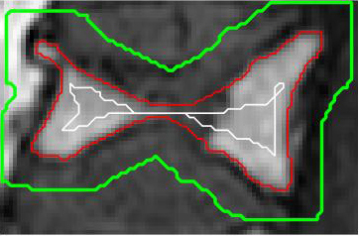

The balance induced by the weights produces smoother borders at regions with small pixel intensities. Moreover, as long as the interior annotation contains small portions of the dark and bright regions, it can work well even with rough interior and exterior seed points. To better illustrate this, Figure 3 shows a few iterations of BGrowth for a single vertebral body segmentation. Note that, at iteration 5, a few dark regions (outside of the vertebral body) are still part of the foreground and, as the balancing goes on, the foreground shrinks towards the ground-truth. The final result is quite close to the manual segmentation. Figure 4 shows another example of BGrowth’s iterations on five lumbar vertebrae. Note that, the method works quite well even when a simple line is given as seed points. The only constraint is that the interior annotation has to comprise the dark/bright regions within the vertebral body.

![]() |

| Annotations | Iteration 1 | Iteration 5 |

| Iteration 10 | Iteration 20 | Iteration 50 |

As we work with the balance of old and new strength factors, it might happen that the process of expansion goes back and forth on the same pixel. Therefore, we would recommend the definition of a maximum number of iterations depending on the kind of image being segmented. We have empirically used a maximum of 30 iterations for the segmentation of a single vertebral body. For a whole exam, as exemplified in Figure 4, a few more iterations might be necessary.